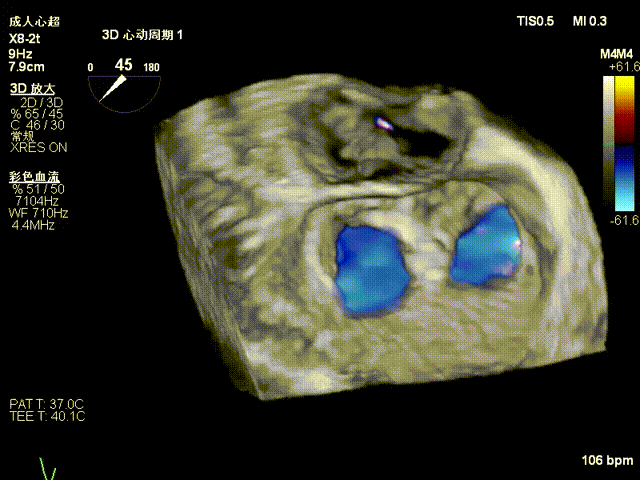

术前3D上彩

释放后评估反流